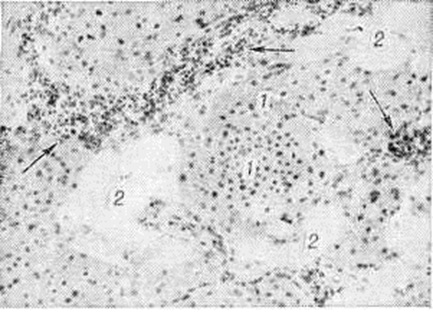

Миобластома зернисто-клеточнаяМиобластома зернисто-клеточная (греческий mys, my[os] мышца + blastos росток, зародыш + -onia; синонимы: зернисто-клеточная опухоль, миобластомиома, миома из миобластов, опухоль Абрикосова) — опухоль мышечной ткани, характеризующаяся зернистым строением цитоплазмы клеток и, в основном, доброкачественным течением. Впервые Миобластома зернисто-клеточная описана в 1854 год Вебером (Weber) и детально изучена в 1926 год А. И. Абрикосовым. Миобластома зернисто-клеточная встречается в любом возрасте. Опухоль чаще располагается в языке, мышцах верхних и нижних конечностей, встречается также в коже, гортани, дёснах и гипофизе. Макроскопически Миобластома зернисто-клеточная имеет вид узла величиной до 3,5 сантиметров в диаметре, беловато-розового, иногда белесоватого цвета на разрезе, не всегда чётко отграниченного от окружающих тканей. В редких случаях опухолевые узлы Миобластома зернисто-клеточная могут иметь гигантские размеры — до 20 сантиметров и более в диаметре. Микроскопически опухоль состоит из комплексов крупных, величиной от 40 до 100 микрометров в диаметре, овальных, полигональных, иногда вытянутой формы клеток (рисунок), в цитоплазме которых содержатся крупные, равномерно расположенные зерна, дающие слабоположительную реакцию на липиды и ШИК-реакцию; иногда в цитоплазме клеток Миобластома зернисто-клеточная обнаруживаются капельки жира. Ядра опухолевых клеток округлой формы, расположены центрально; фигуры митоза обычно отсутствуют, однако часто бывают видны ядра с перетяжкой или делящиеся амитотическим путём. Строма нежноволокнистая, бедная сосудами. Гистогенез Миобластома зернисто-клеточная не выяснен. Обнаружение в её клетках миофибрилл и формирование атипических мышечных волокон являются, по мнению А. И. Абрикосова и некоторых других исследователей, признаком происхождения Миобластома зернисто-клеточная из миобластов; обнаружение в опухоли миелина, леммоцитов (шванновских клеток), нервных волокон позволяет ряду других исследователей предполагать нейрогенное происхождение опухоли. |